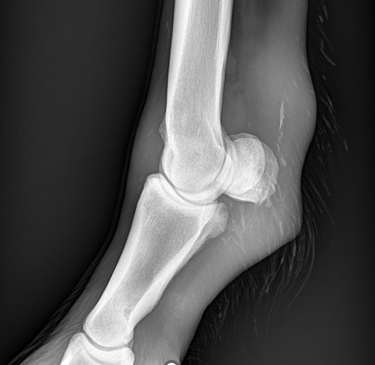

Is uw paard mank, hoefbevangen of is er een vermoeden van een halsprobleem? Dan kan het aangewezen zijn om een radiografisch onderzoek (RX) aan huis uit te voeren. Wij beschikken over een digitaal mobiel radiografietoestel, waardoor opnames eenvoudig bij u ter plaatse kunnen worden gemaakt.

Wij maken geen radiografische opnames in het kader van een radiografische keuring.

Dit onderzoek wordt uitgevoerd binnen een straal van 20 km rond de praktijk.

Radiografie (RX)

Consult op de praktijk of aan huis